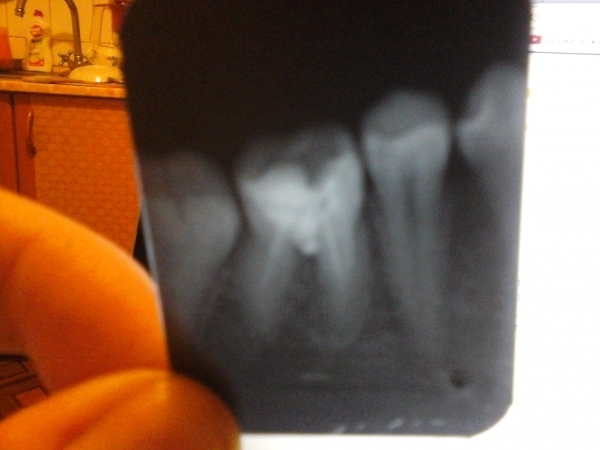

Я пошла в поликлинику с острой зубной болью. Мне запломбировали каналы и поставили временную пломбу, я сильно заболела и поэтому долго с ней проходила. Сейчас пошла в платную поликлинику долечивать этот зуб. Сделали снимок, сказали, что каналы были плохо запломбированы и что там началось воспаление корней. Внешне нет никаких опухолей. Сказали удалять зуб.

Пожалуй, соглашусь с докторами из второй клиники.

На одном из корней имеется большой очаг воспаления, а также не совсем понятна ситуация в месте бифуркации (раздвоении) корней.

Зуб придется удалить.